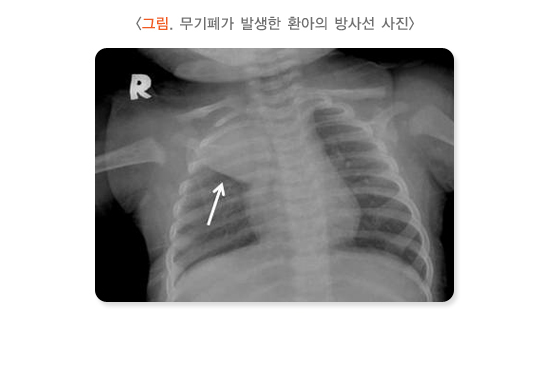

1) 가슴 X-선 검사

가슴 X-선 검사는 모든 환자에게 시행할 필요는 없습니다. 그러나 증상이 심해 입원해야 하거나, 특히 열이 있다면 폐렴이 동반됐는지 확인하기 위해 시행합니다. 좁아진 세기관지를 통해 공기가 잘 빠져나오지 못하므로 폐 전반에 걸친 과팽창 소견을 보입니다. 어린이는 이물 흡입으로 인해 기관지나 세기관지가 막혀 천명이 발생할 수 있습니다. 이를 세기관지염으로 오인할 수 있으므로 병력 청취와 진찰 소견으로 이물 흡입이 의심된다면 가슴 X-검사를 시행하여 확인합니다.

- 가래로 인해 기관지가 막혀서 무기폐 발생